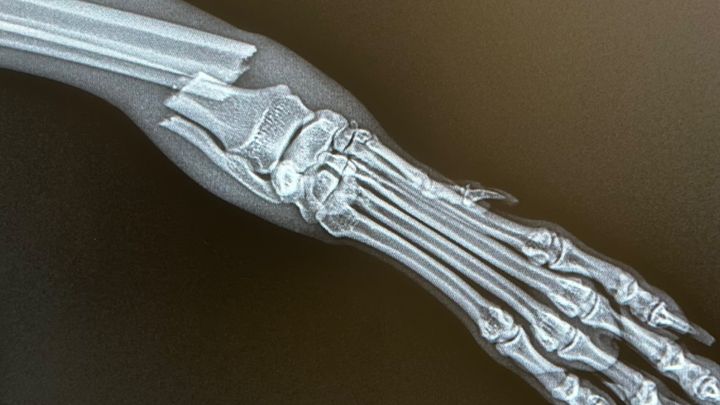

Hi, I’m Sabrina a Vet technician. We rescued a little Greyhound of 1 year old at my job. He jumped from a high place at his house, his paw is broken but the owners couldn’t pay 5000$.

he is young and as potential so we want to give him a chance. We could save his entire paw with the surgery, or we will amputate his entire leg for his confort since it is less expensive. If we wait too long, the paw cannot be fixed…